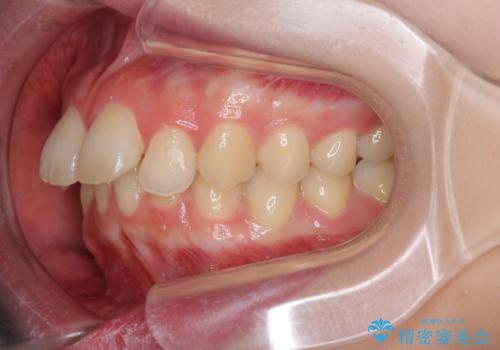

- 口元の突出感を気にして来院された患者様です。

左右ともに上顎奥歯が外を向き、下顎奥歯が内側に倒れているシザーズバイトであったため、補助装置により改善することとしました。

上下の咬み合わせは、下顎に対して上顎が相対的に前方にあったため、奥歯のシザーズバイト改善後に上顎左右第一小臼歯2本を抜歯し、上顎前突を改善していくこととしました。